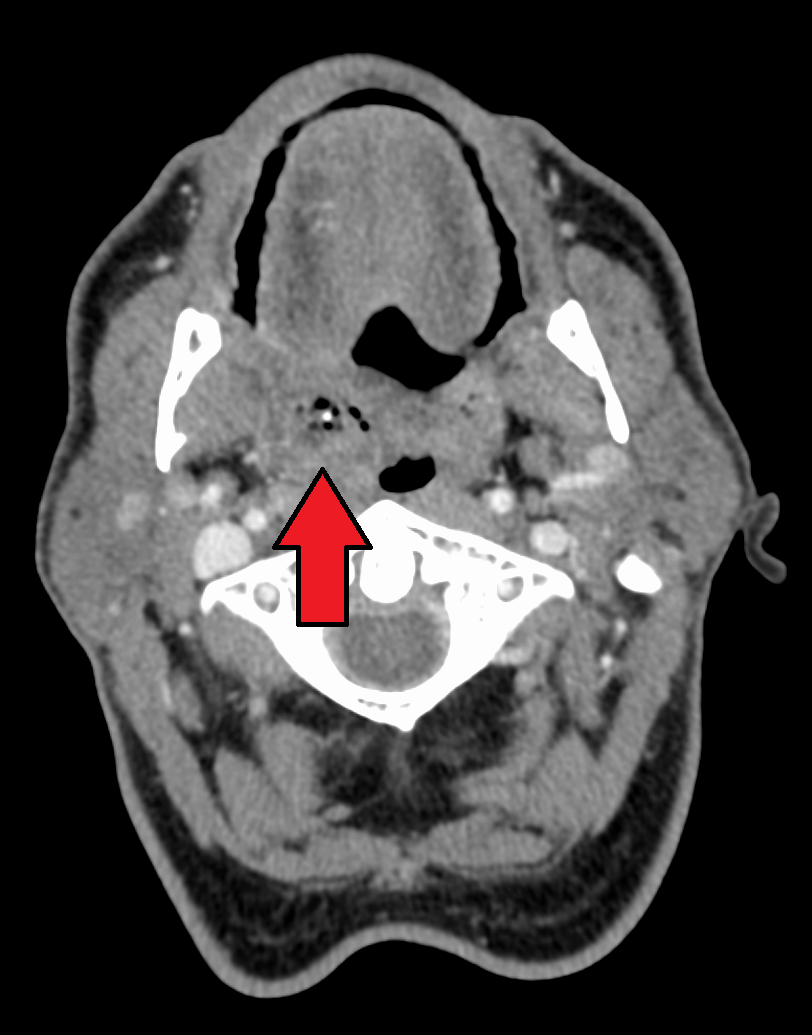

진단은 대개 증상을 기반으로 한다.[2] 의학 영상을 시행하여 합병증을 배제할 수 있다.[2] CT 스캔, MRI, 초음파가 진단에 유용하다.[2]

진단은 대개 증상을 기반으로 한다.[2] 의학 영상을 시행하여 합병증을 배제할 수 있다.[2] CT 스캔, MRI, 초음파가 진단에 유용하다.[2]